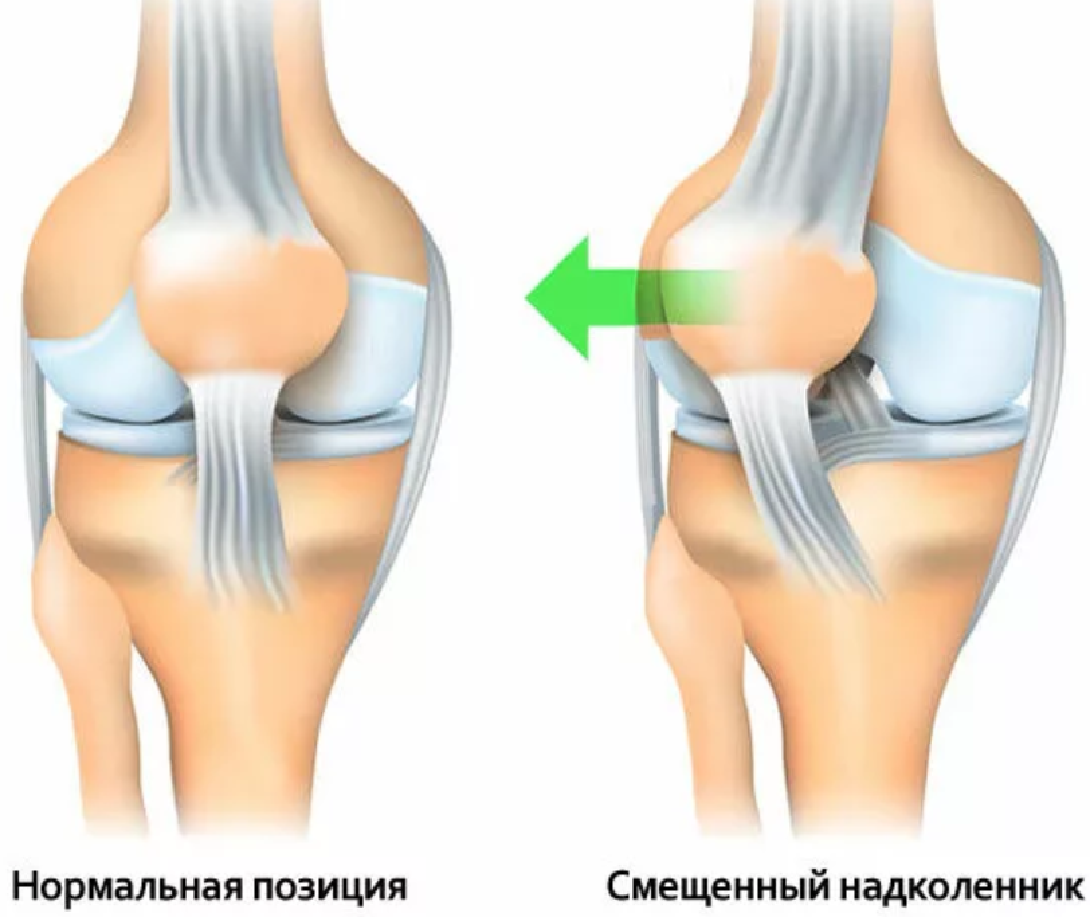

Проблемы с коленным суставом: флоттация и лечение